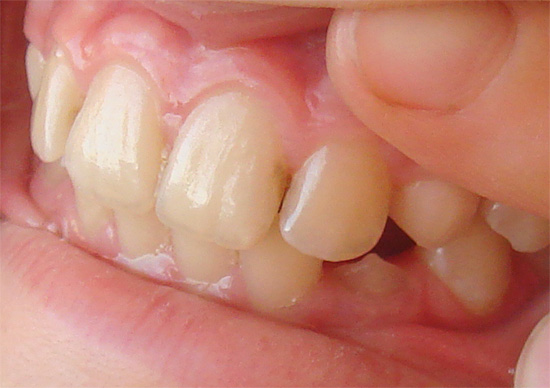

In rari casi, l'area interessata si espande verso le aree adiacenti di smalto e con uno sguardo più attento al dente si notano macchie scure. La foto sotto mostra un esempio di tale carie nascosta sotto un vecchio sigillo: